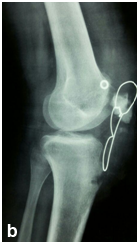

Male patient 20 years old was exposed to truma lead to avulsion of distal patellar pole Figure 1. The patient underwent management by excision of the distal pole of the patella and direct repair of the tendon to the rest of the patella. Three months later he was exposed to another truma to the knee lead to rerupture of the suture again with tense knee effusion, his seeked medical advice and aspiration was done.

• Figure 1 Preoperaive plane X-rayes shows small sized parella and very high in front of the trochles.